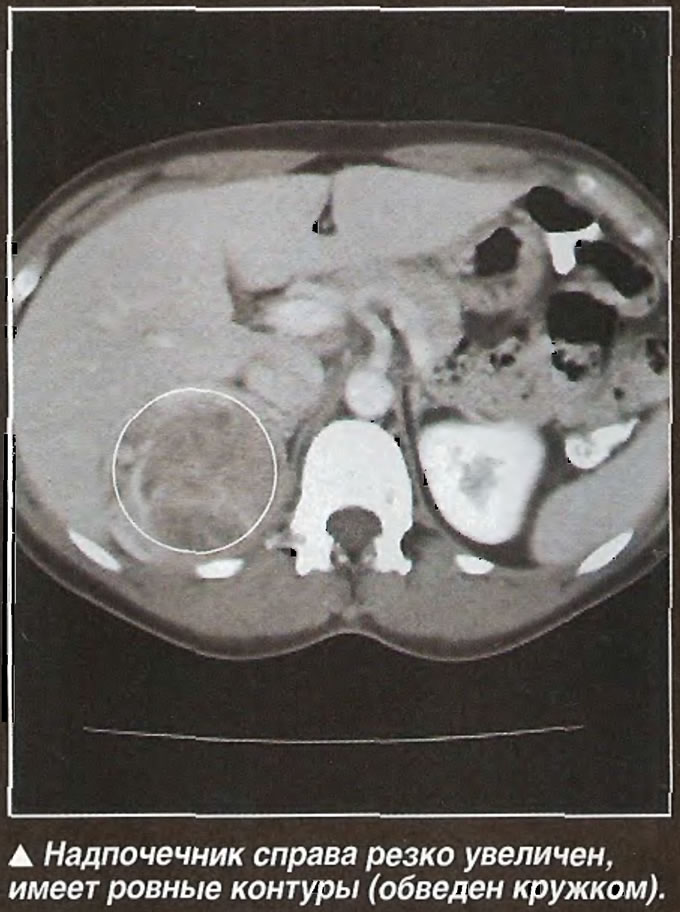

Рак правого надпочечника

Женщина обратилась к врачу с жалобами на рост волос на лице, огрубление голоса и отсутствие менструаций. Такие симптомы указывали на избыточное образование в организме больной мужских половых гормонов. Вероятным источником их синтеза была опухоль надпочечника. Значительное увеличение органа и гиперпродукция мужских половых гормонов позволили предположить злокачественный характер новообразования, несмотря на ровный внешний контур. Впоследствии диагноз был подтвержден гистологически.